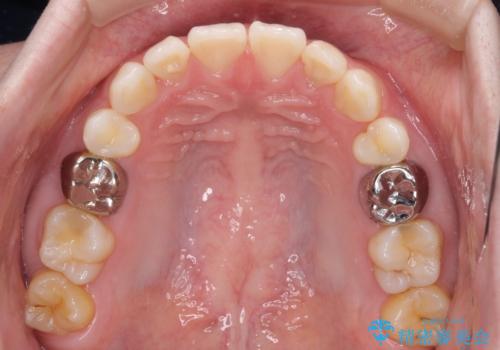

萌出が不十分な歯はインビザラインで引き出すことができないため、ワイヤー装置などの併用が必須となります。

今回は部分的にワイヤー矯正を用いましたが、右下の乳歯は全く動かなかったため、抜歯をした上でインプラントを埋入し、オールセラミッククラウンにて補綴治療を行いました。